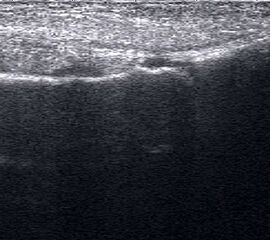

Längsschnitt über dem Lig. fibulocalcaneare. Die Peronealsehnen erscheinen als echoreiche runde bis ovaläre Struktur.

Abbildung 19

Lagerung: Rückenlage, OSG in Neutralstellung.

Schnittebene: LS über Lig. fibulocalcaneare.

Referenzstrukturen: Fibulaspitze und Talus.

Befunde: Das Lig. fibulocalcaneare is nativ schlecht abgrenzbar, da es in die Tiefe und nicht parallel zum Schallkopf verläuft. Direkt über das Band ziehen quer getroffen die Peronäussehnen. Durch die Distorsion kann auch das Peritendineum peroneale einreißen. Die Peronealsehnen sind dann in ihrer Sehnenscheide von Blut umgeben, was sich als echoarmer Ring (Halo-Phänomen) darstellt und ein indirektes Zeichen für eine Verletzung des Lig. fibulocalcaneare ist.